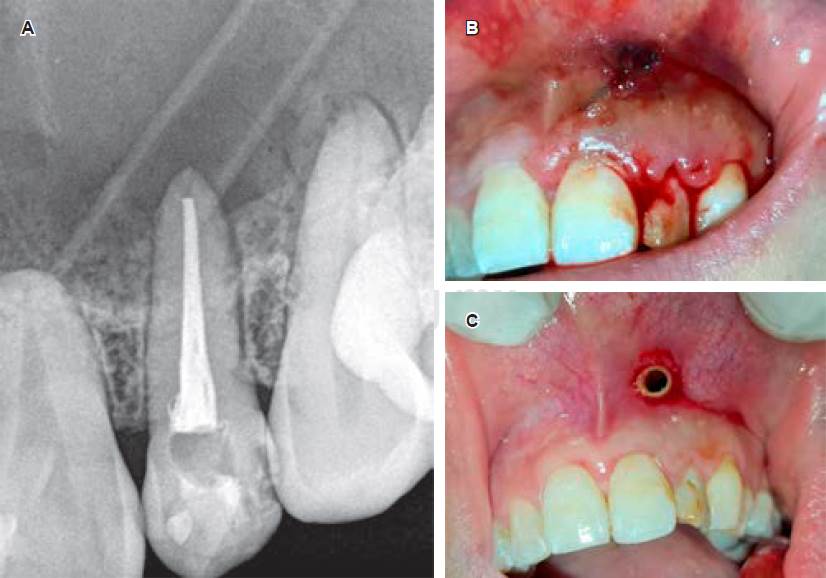

La Figura 3A y B evidencian la radiografía y la clínica inmediata a la colocación del drenaje por don de la paciente realizaba los lavados. En la Figura 3C se puede observar normalidad de los tejidos circundantes al catéter; esta fotografía fue tomada a los cuatro meses de la colocación inicial durante un procedimiento de reemplazo del dispositivo.

Figura 3 Colocación de drenaje con fines descompresivos. A) Radiografía postendodoncia y colocación inmediata de drenaje. B) Se puede observar la sutura del tubo de drenaje a la mucosa alveolar. C) Mucosa sana circundante al drenaje, fotografía obtenida durante un procedimiento de reemplazo del tubo siliconado.